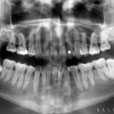

Cuatro pacientes jóvenes, acuden a la consulta para realizarse estudios radiográficos previo tratamiento ortodóntico. En la radiografía panorámica (fig. 1) se observa los terceros molares inferiores semiimpactados en posición horizontal. En la radiografía panorámica (fig. 2) se observa los cuatro terceros molares totalmente impactados; el tercer molar superior derecho se encuentra en posición vertical, el tercer molar superior izquierdo en posición mesioangular y los terceros molares inferiores en posición transversal. En la radiografía panorámica (fig. 3) los terceros molares superiores se encuentran totalmente impactados en posición vertical; el tercer molar inferior derecho semiimpactado en posición horizontal, el tercer molar inferior derecho en posición mesioangular y el tercer molar inferior izquierdo semiimpactado en posición mesioangular. En la radiografía panorámica (fig. 4) se observa el tercer molar inferior derecho totalmente impactado en posición invertida, el tercer molar inferior izquierdo semiimpactado en posición vertical.

Dientes impactados son aquellos que siguen formándose dentro del hueso pero fracasan en el proceso de erupción a causa de falta de espacio o por estar obtaculizados por alguna barrera física (quistes o tumores odontógenos). Cualquier diente puede estar impactado pero los más frecuentes son los terceros molares y los caninos superiores. Los terceros molares impactados se clasifican según su orientación dentro de la arcada dentaria , así se pueden presentar en posición mesioangular,distoangular,vertical, horizontal e invertida. Si se encuentran rodeados totalmente por hueso se consideran como impactados total y si se encuentran parcialmente en el hueso y parcialmente en tej. blando se consideran semiimpactados La impactación de los dientes muchas veces puede pasar inadvertida y se descubre mediante una radiografía , pero también pueden ocasionar complicaciones como reabsorción radicular del diente adyacente, infección, dolor asociado ,predisposición a la formación de quistes dentígeros y reabsorción externa